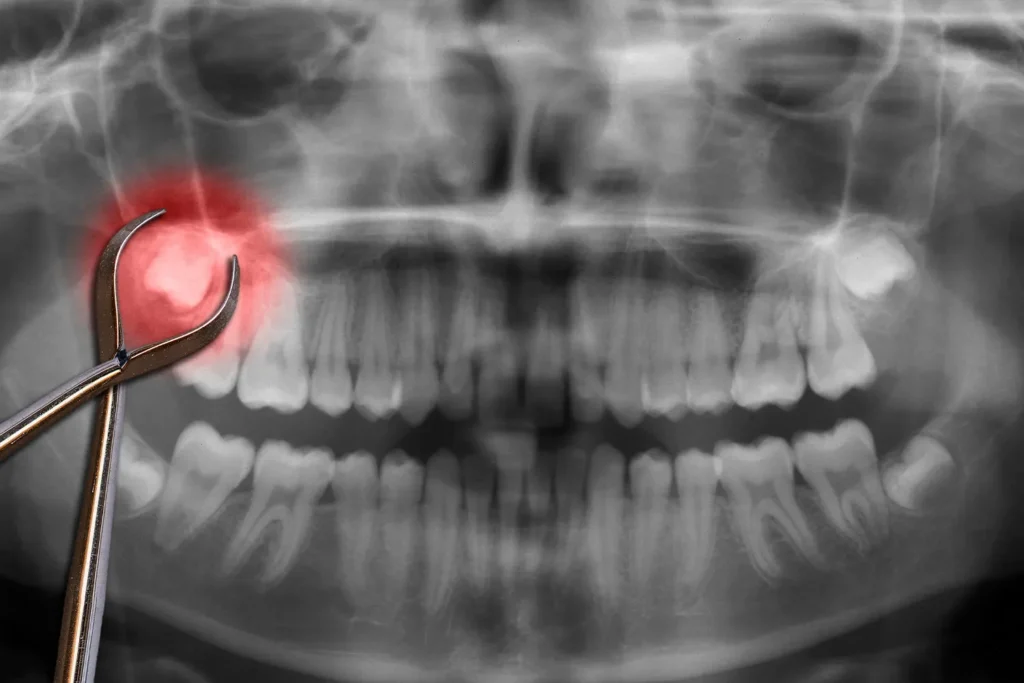

Your Hendersonville dentist will first examine your wisdom tooth and take x-rays to check the tooth’s size, position, and orientation in the jaw. This also helps determine any complications affecting your wisdom tooth and other teeth. After, the dentist will inject anesthesia into the gums near the wisdom tooth to numb the area.

Once the anesthesia takes full effect, your dentist will use an elevator to “elevate” and loosen the tooth from its socket. Afterwards, they’ll use dental forceps to grab the wisdom tooth and rock it back and forth until it comes off its socket. They’ll then place a gauze pad on the extraction site to stop the bleeding.